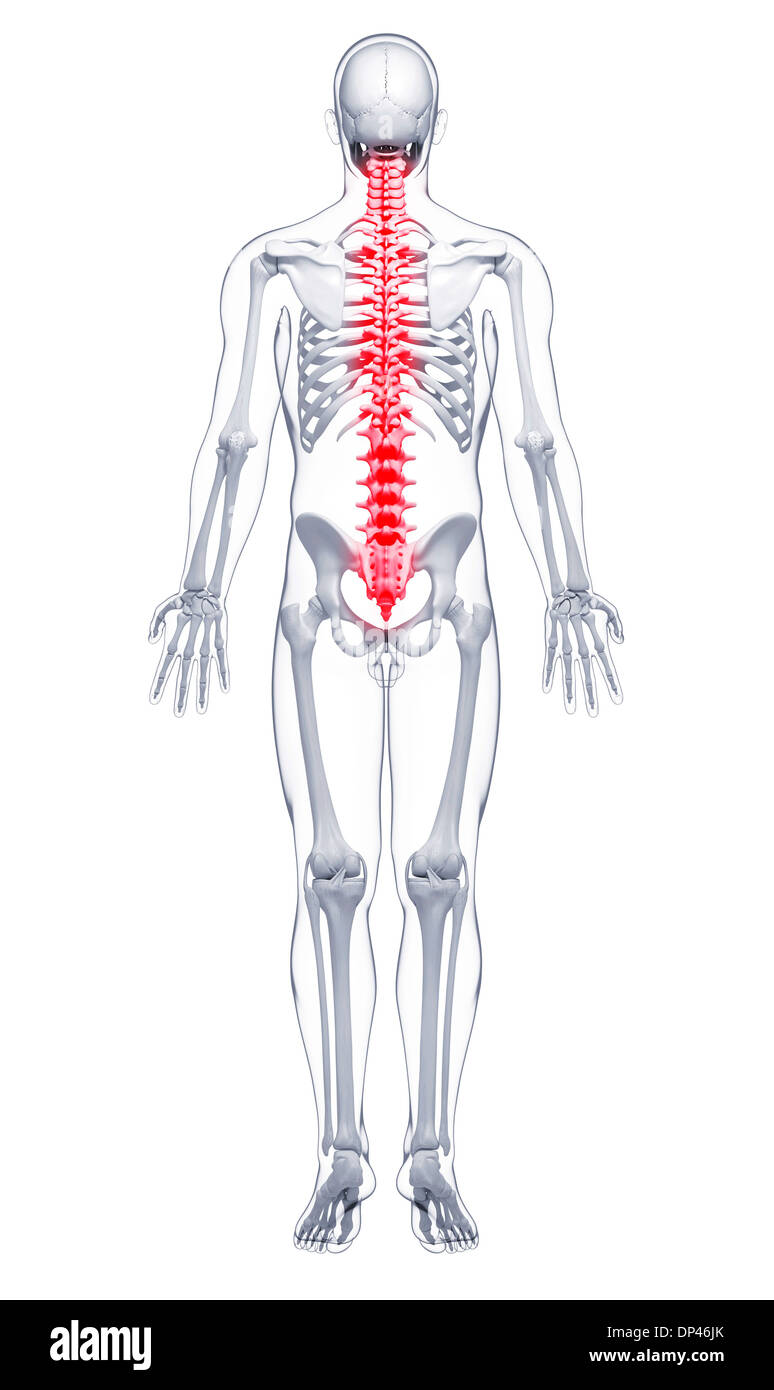

La douleur de la colonne vertébrale, artwork Banque D'Imageshttps://www.alamyimages.fr/image-license-details/?v=1https://www.alamyimages.fr/la-douleur-de-la-colonne-vertebrale-artwork-image65246571.html

La douleur de la colonne vertébrale, artwork Banque D'Imageshttps://www.alamyimages.fr/image-license-details/?v=1https://www.alamyimages.fr/la-douleur-de-la-colonne-vertebrale-artwork-image65246571.htmlRFDP46JK–La douleur de la colonne vertébrale, artwork